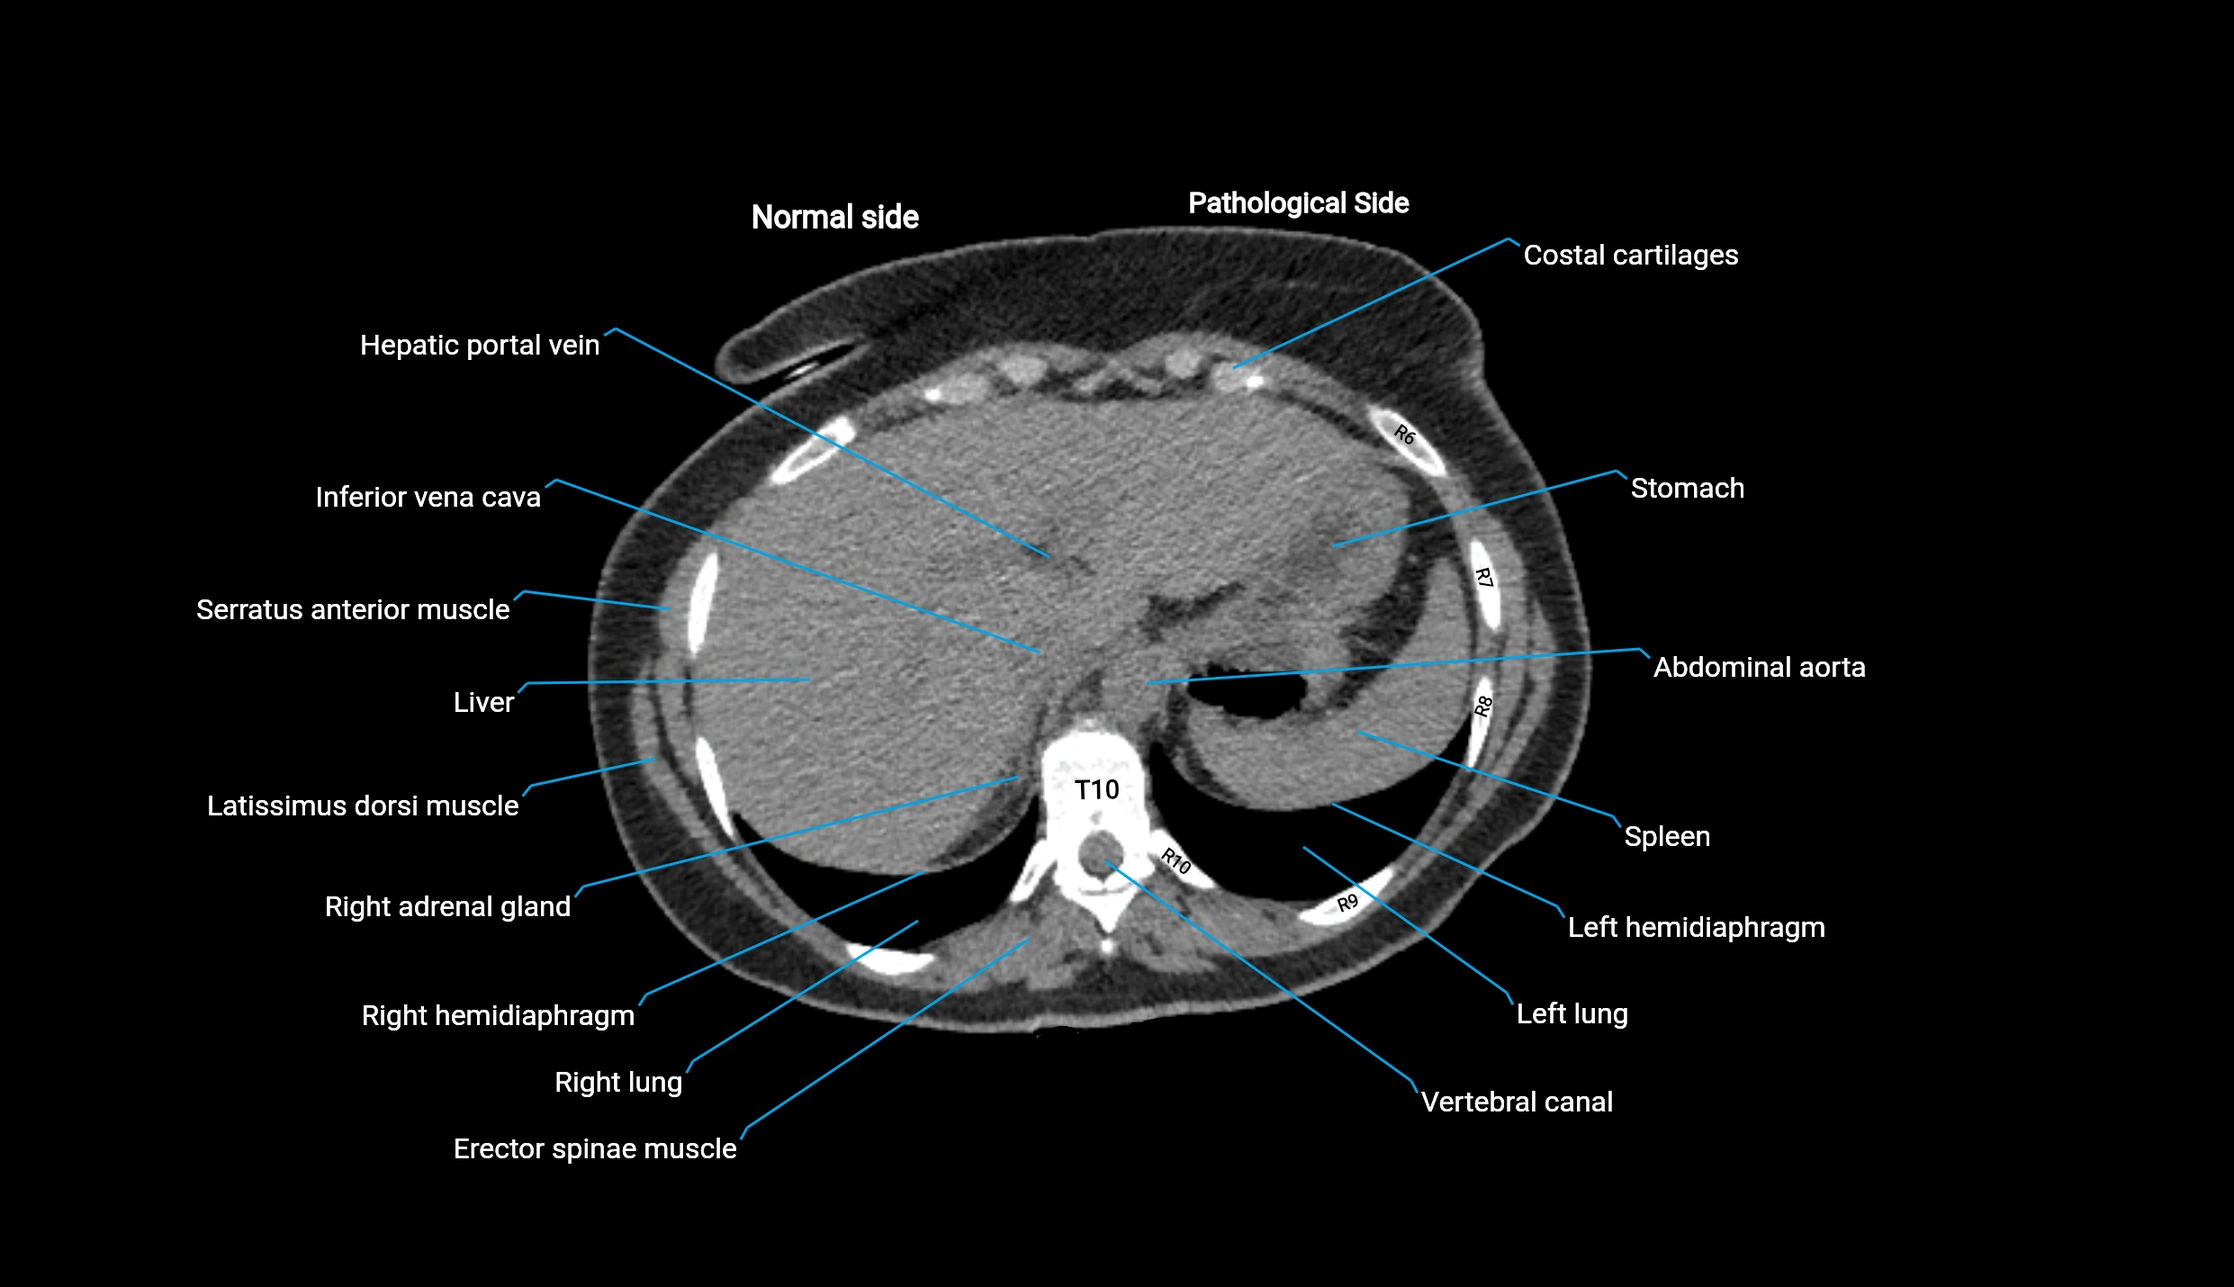

CT image

image